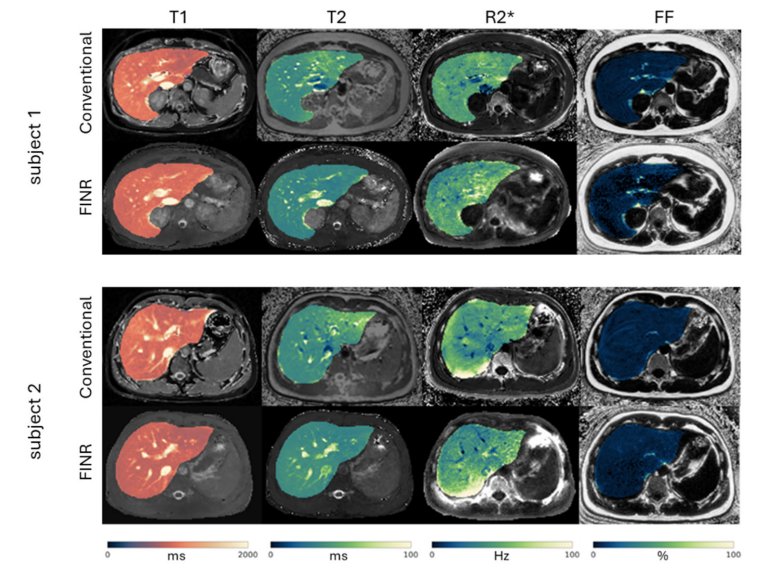

2. Navigator motion-resolved MR fingerprinting using implicit neural representation (FINR) feasibility for free-breathing 3D whole-liver multiparametric mapping.png

Li C, Li J, Zhang J, Solomon E, Dimov A, Spincemaille P, Nguyen T, Prince M, Wang Y

Magnetic Resonance in Medicine, 2025